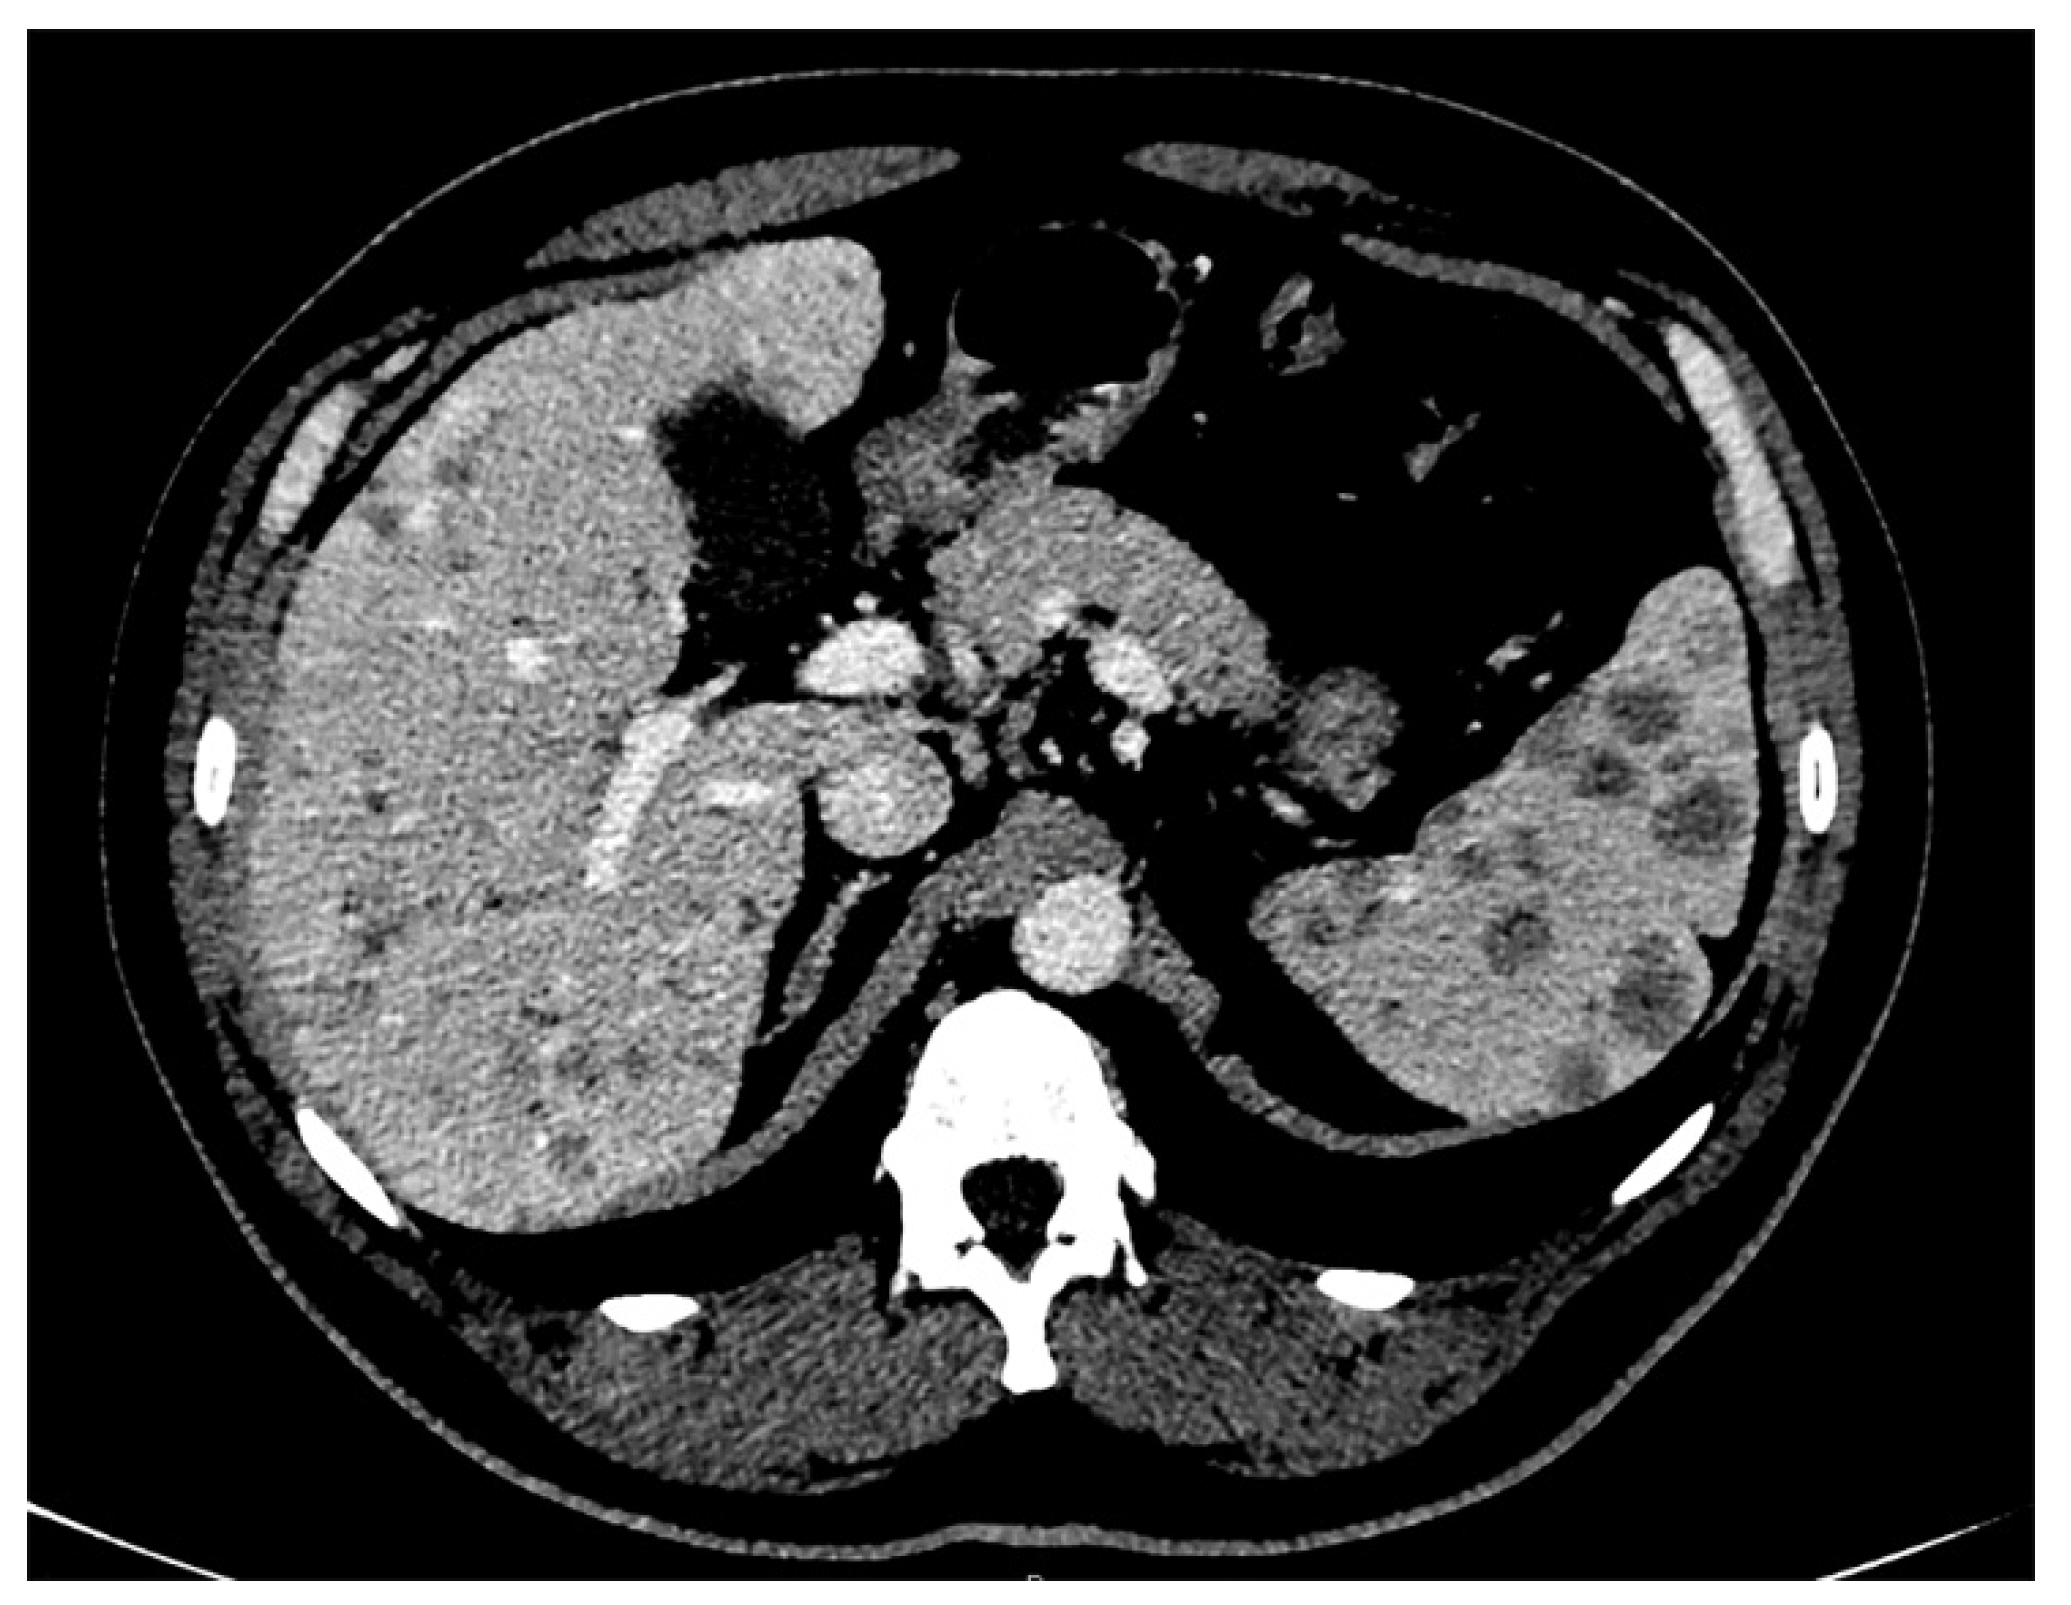

Figure 3.

Abdominal contrast-enhanced computed tomography, in portal phase, showed multiple nodules ranging from 1.0 or 2.0 mm to 0.75 cm in diameter diffusely distributed in the liver, and ranging from 1.0 mm to 2.0 cm in the spleen.